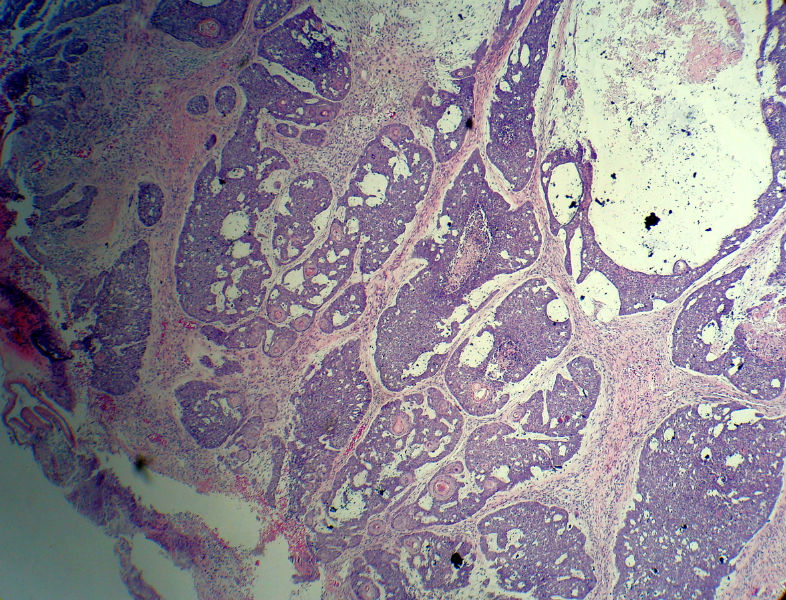

后枕部肿物

男,49岁,后枕部肿物3年,偶有破溃出血。

大体:皮肤半球形隆起,大小约2.3×2厘米,高出皮表0.8厘米,切面灰白,质地细腻。

似乎既有腺样结构,也有角化珠形成,还有细胞团内的粉刺样坏死。

有坏死、囊肿、钙化及胆固醇样裂隙等结构

考虑外毛根鞘肿瘤,局部癌变。

大部分区域看着象基底细胞癌,后面几张(11-14)看着象是鳞癌。综合考虑基底细胞样鳞癌。